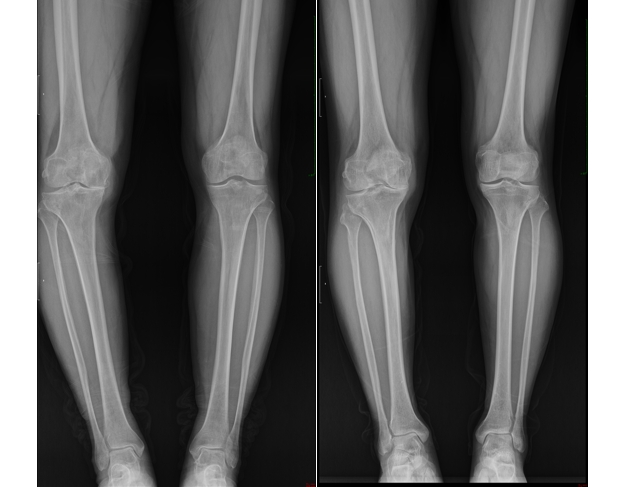

考虑到哥哥年龄偏大,且病情主要集中在膝关节内侧,内侧胫股关节面磨损严重,而外侧及前后交叉韧带功能尚好,谭红略主任团队决定为他实施单髁表面置换术。这一手术精准替换受损的膝关节部分,保留了健康组织,术后张伯伯恢复迅速,不仅疼痛大幅减轻,行走、上下楼梯等日常活动也变得轻松自如。

而对于相对年轻的弟弟,尽管同样遭受膝关节炎的困扰,但他的情况却有所不同。作为一位热爱运动、活动量较大的人,他的膝关节磨损并不均匀,且年龄尚轻,谭红略主任团队选择了股骨下端闭合截骨术。这一手术通过调整下肢力线,减轻特定区域的压力,有效延缓了关节炎的进展,同时保留了自然关节的功能。术后,弟弟不仅疼痛消失,更重要的是,他得以继续享受运动带来的快乐,生活质量显著提升。